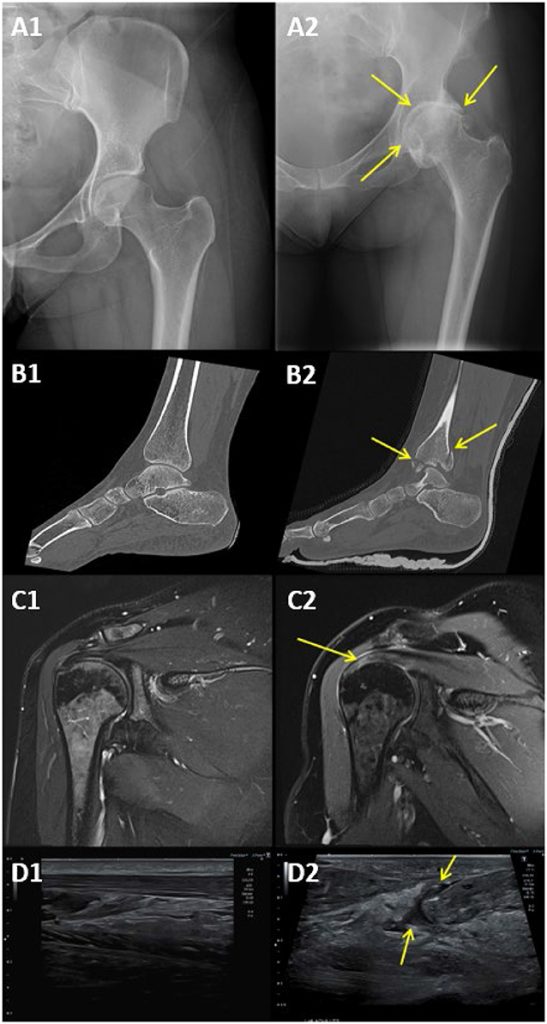

Nogle gange kan det, der føles som et muskuloskeletalt problem, faktisk være noget andet! For eksempel kan smerter, du føler i knogler og muskler, faktisk komme fra en anden del af kroppen, såsom hjertet eller nyrerne [1]. Derfor bruger læger forskellige billedteknikker, ikke kun for at se på knogler og muskler, men også for at udelukke andre tilstande, der kan forårsage smerter (figur 1).

To søjler inden for billedteknologi, der næsten altid er gode valg til at se på knogler, er røntgenstråler og computertomografi (CT)-scanninger. Røntgenstråler er et af de ældste og mest almindelige billedværktøjer inden for ortopædi, som er den gren af medicinen, der behandler bevægeapparatet. Røntgenstråler virker ved at sende usynlige stråler ind i kroppen. Da knogler er tættere end muskler og andet væv, absorberer de flere stråler. Dette skaber et specielt billede, hvor knoglerne fremstår hvide på røntgenbilledet, mens luft og det bløde væv vises sorte eller grå, så lægerne kan se, hvad der foregår indeni! Læger tager normalt et par røntgenbilleder fra forskellige vinkler for at få et godt overblik over anatomien fra alle vinkler.

Røntgenbilleder er gode til at påvise brud, ledforskydninger og gigt, men når der er behov for flere detaljer, bruger lægerne CT-scanninger. CT-scanninger bruger røntgenstråler til at tage flere billeder fra forskellige vinkler rundt om kroppen for at danne et 3D-billede af knogler og led. Dette er især nyttigt ved komplicerede brud, såsom brud i rygsøjlen eller store traumer, og det er også nyttigt til planlægning af operationer. Du undrer dig måske over, hvorfor vi ikke bare bruger CT-scanninger til alle – godt spørgsmål! En af hovedårsagerne til, at læger undgår CT-scanninger, er, at de udsætter kroppen for en stor mængde stråling, som er en form for usynlig energi [2]. Nogle former for stråling, f.eks. lys, er helt sikre. Men andre former, f.eks. røntgenstråler, kan være skadelige, hvis man får for meget, især i en ung alder.

Magnetisk resonansbilleddannelse, eller MR, er en af de bedste måder at se blødt væv som muskler, sener, ledbånd og brusk (figur 2A). MR-scanning er især nyttig til at opdage problemer som revet ledbånd, senebetændelse og bruskskader i leddene. MR-scanneren ligner en kæmpe donut, og patienten ligger ned i midten af donuten for at få taget billeder. I modsætning til røntgenstråler eller CT-scanninger, der udsætter patienterne for stråling, bruger MR-scanning kraftige magneter til at skabe detaljerede billeder. Derfor er det nogle gange en sikrere løsning, især for yngre patienter. Ulempen? MR-scanninger tager lang tid, nogle gange op til en time, og patienterne skal ligge helt stille hele tiden, ellers kan billedet blive sløret. Det laver også meget høje lyde, som nogle mennesker kan finde ubehagelige. Da magneten er så stærk, er MR-scanning ikke altid sikker for mennesker med visse metalliske enheder i kroppen, såsom visse pacemakere til hjertet.

En anden god mulighed, som læger har for at se blødt væv som muskler, sener og ledbånd, er ultralyd (figur 2B). Interessant nok kan den samme ultralydsmaskine, der bruges til at se et barn inde i en gravid mor, også bruges til at diagnosticere problemer med bevægeapparatet. Ultralyd fungerer ved at sende lydbølger gennem en lille enhed kaldet en. Bølgerne passerer derefter gennem kroppen og reflekteres af forskellige væv for at give et realtidsbillede på skærmen. I modsætning til røntgenstråler eller MR-scanning kan ultralyd vise bevægelser i realtid. Dette gør det særligt nyttigt til at styre injektioner af medicin i leddene for at hjælpe med slidgigt og til at observere bevægelser i muskler, sener og led. Ultralyd er også bærbart, hurtigt og bruger ikke stråling. Men ligesom alt andet har ultralyd nogle begrænsninger. Et af de største problemer med ultralyd er, at det ikke kan se særlig godt inde i leddene, fordi lydbølgerne reflekteres af knoglerne i stedet for at passere igennem dem. Desuden afhænger billedernes nøjagtighed af den persons færdigheder, der bruger det [3].